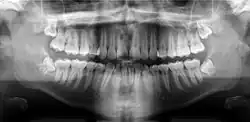

Orthopantomogramme

Un orthopantomogramme, abrégé par les sigles OPT ou OPG, est une radiographie panoramique de toute la denture. À ce titre, cet examen est plus souvent appelé « panoramique dentaire ».

Il consiste en une mise à plat de l'arc dentaire, d'une oreille à une autre.

Radiographie panoramique dentaire

Le cliché panoramique donne une vue d’ensemble des arcades dentaires, des maxillaires, des articulations et des sinus. Il est utilisé pour diagnostiquer un grand nombre de conditions pathologiques : infections, fractures des mâchoires, kystes et granulomes à la racine des dents, et certaines affections osseuses (maladie de Paget)…

On effectue aussi un panoramique dentaire pour évaluer la distribution des dents, la perte osseuse et les parodontites, ou encore pour visualiser l’ensemble des germes de dents chez l’enfant, pour définir son âge dentaire. Par ailleurs, il s’avère également utile pour décider du bien-fondé de la pose d’implants ou de la localisation des racines artificielles avant leur pose.